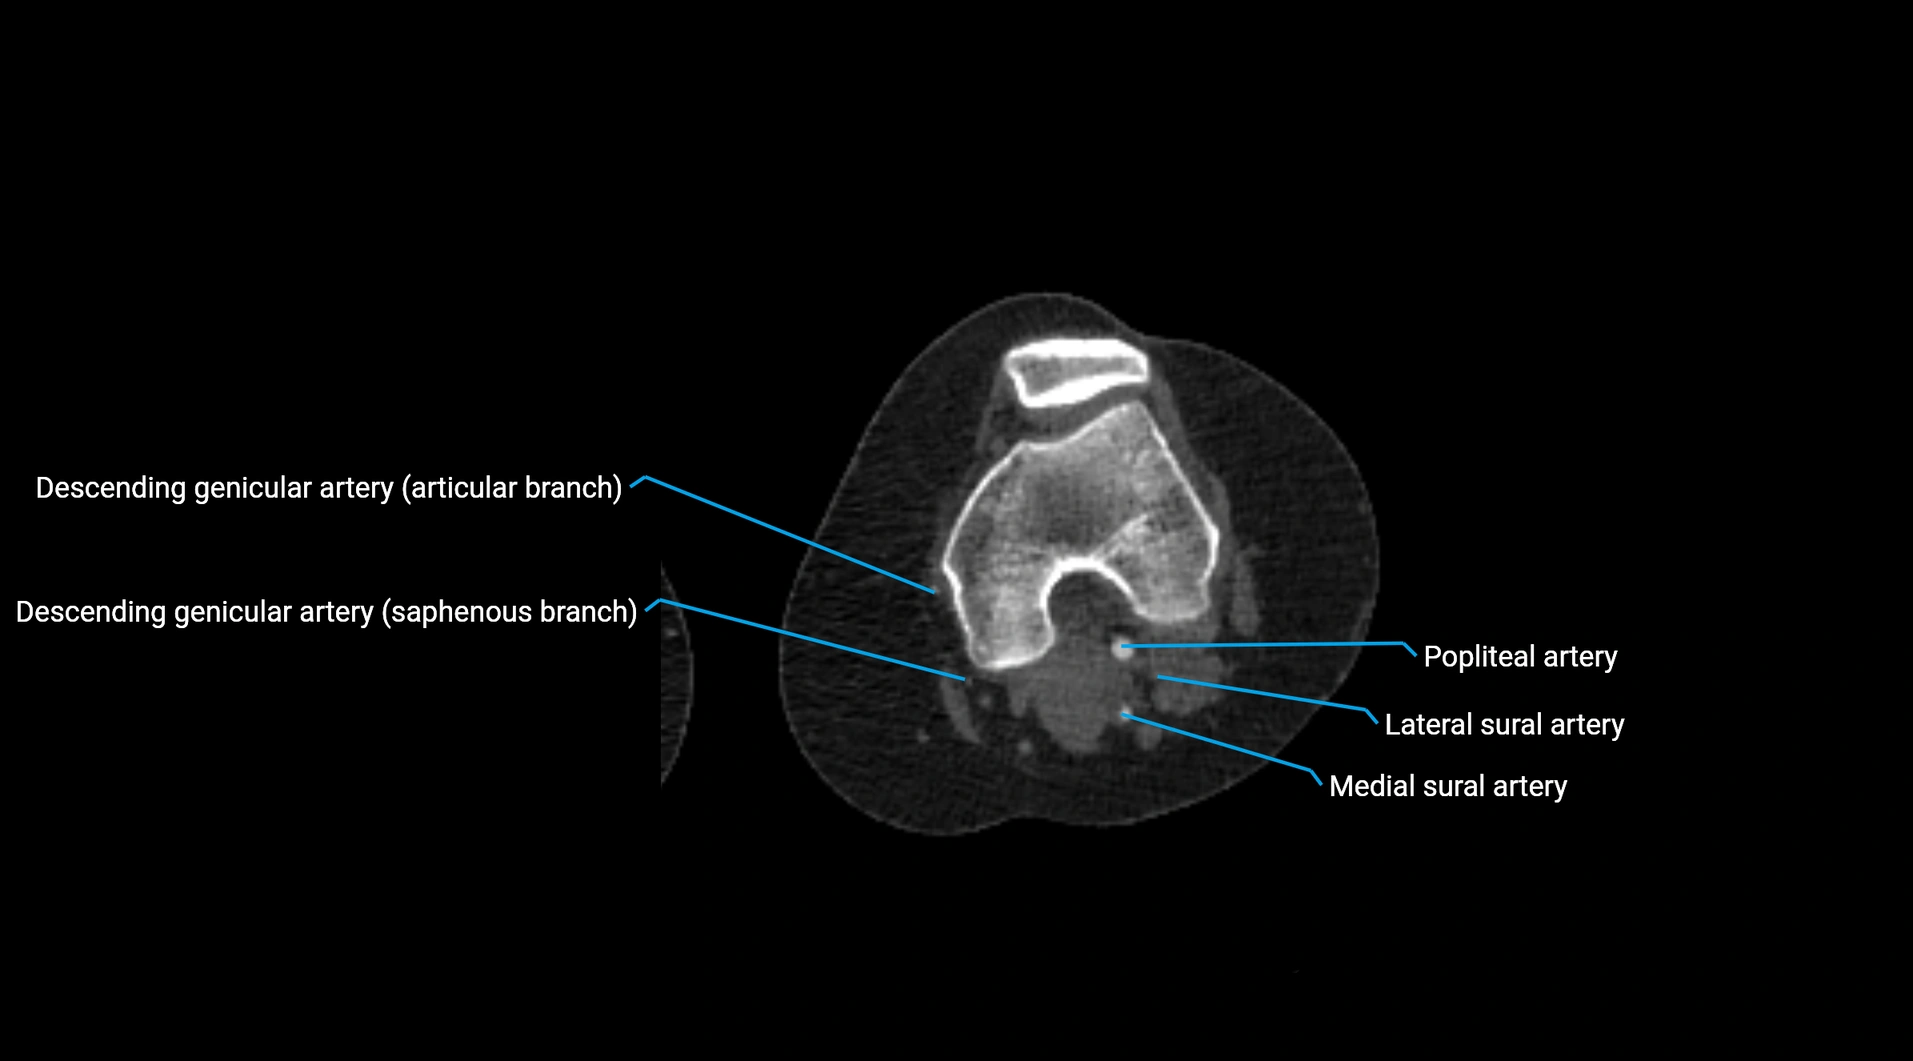

Contrast-enhanced CT (CTA):

• Gold standard for abdominal aortic imaging

• Provides excellent detail of lumen, wall, aneurysm, thrombus, and branch vessels

• Multiplanar and 3D reconstructions help in aneurysm measurement, stent graft planning, and dissection evaluation

• Detects acute rupture, traumatic injury, or occlusion with high sensitivity